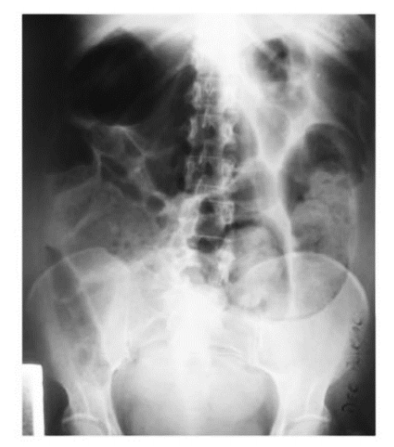

Paciente masculino, 55 anos, queixa-se de ferida em MID há 7 anos. Apresenta HAS, DM e sobrepeso, além de edema de MMII e peso e cansaço ao final do dia. Relata que sintomas melhoram com repouso e elevação dos membros. Foi realizado um Ecodoppler venoso de membros inferiores que diagnosticou refluxo em toda veia safena Magna e sem evidências de trombose antiga em membro inferior direito. Pulsos arteriais simétricos e presentes.

Sobre esse caso clínico, qual é a sua classificação CEAP?